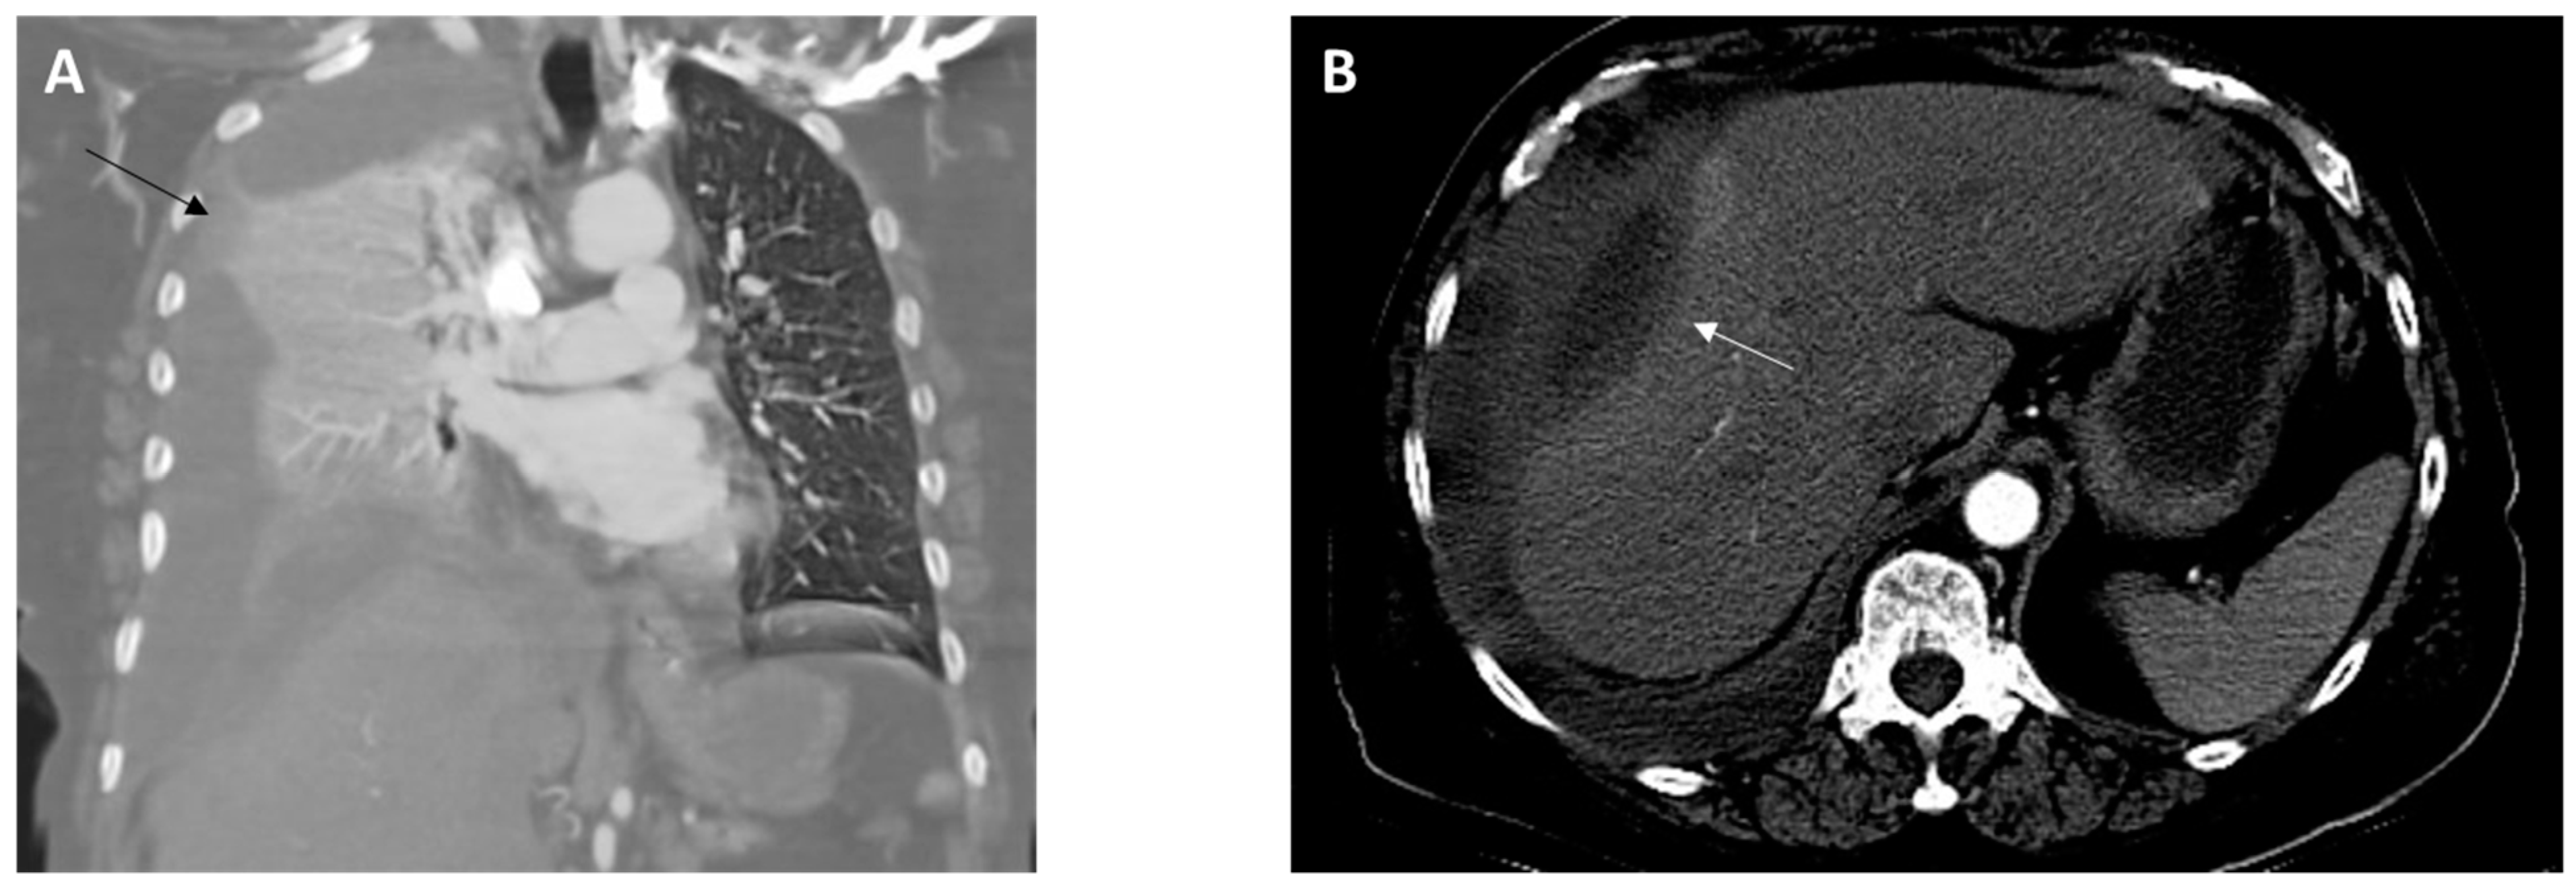

On arrival, she was found to be afebrile but tachycardic (116 beats per minute), tachypneic (26 breaths per minute), and hypoxic (SpO2 60–70% on room air). On physical examination, there was diminished air entry in the right lung and poor oral dentition, visualized with several loose or missing teeth along with visible tooth decay (dental caries). A complete blood count analysis revealed leukocytosis (25.57 k/µL; reference range, 4.50–11.00 k/uL). A comprehensive metabolic panel was unremarkable except for decreased carbon dioxide (14 mEq/L; reference range, 23–31 mEq/L). Elevated lactic acid (9.4 mmol/L; reference range, 0.5–2.0 mmol/L) and procalcitonin (10.05 ng/mL; reference range, 0.00–0.50 ng/mL) levels were detected. Chest X-ray imaging showed near-complete opacification of the right hemithorax. A computed tomography (CT) angiography of the chest revealed a large right hydropneumothorax with a leftward mediastinal shift (Figure 1A). The pleural fluid crossed the diaphragm, terminating in a thick-walled collection along the lateral aspect of the right lobe of the liver (Figure 1B). She developed progressive respiratory failure, requiring intubation and mechanical ventilation. The patient was administered intravenous (IV) vancomycin and piperacillin/tazobactam and was subsequently transferred to our facility for a thoracic surgery evaluation.

Figure 1. Images from computed tomography angiography of the chest obtained at admission. (A), Coronal view revealing a collapsed right lung due to a large pleural effusion (black arrow). (B), Axial view showing the presence of a perihepatic abscess (10.0 × 3.8 cm) (white arrow).